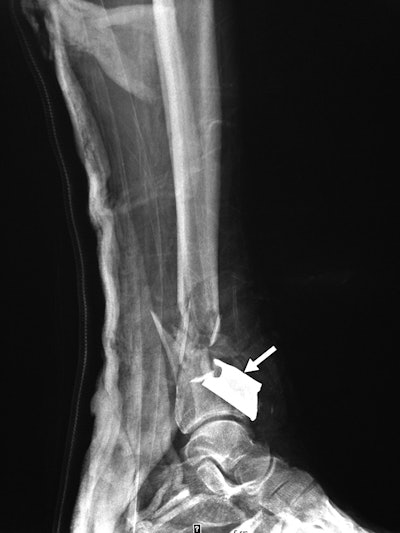

Shrapnel from a secondary blast wave caused a fracture of the distal tibia and fibula in a patient's right leg. All images courtesy of AJR.Clinicians also found a large variety of debris embedded in patents. There were 125 ball bearings, 44 metal fragments, 10 nails, one screw, and nine pieces of gravel or other foreign objects. In addition, 11 patients had fractures in areas including the foot, leg, thigh, hand, orbit, nose, and lumbar spine. Injuries to five of the patients were so severe that they required lower-limb amputations.